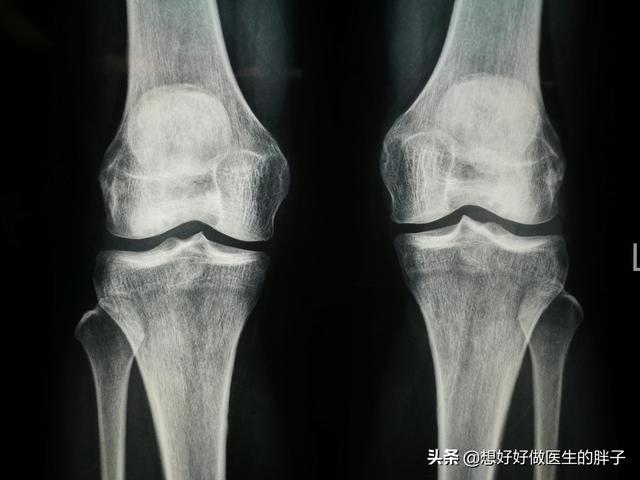

もし患者が変形性関節症による関節痛に苦しんでいるのであれば、病院で適切な検査を行うことをお勧めする。膝のX線フィルムX線検査によって、患者が重度であるかどうかを判断することができる。脂肪骨形成ということなのだろうか?関節腔の狭窄膝の状態について予備的な判断を下す。

レントゲンを撮っても特に問題がはっきりしない場合は、膝関節のMRIを撮って関節腔内の問題を特定します。軟骨や半月板、靭帯などの軟部組織に深刻な問題があるかどうか。

医師は通常、レントゲン写真と膝のMRIに基づいて、患者がどの段階にあるかを判断する。

X線検査では、関節腔の狭小化、関節の過負荷、膝関節全体の関節面の硬化が確認される。